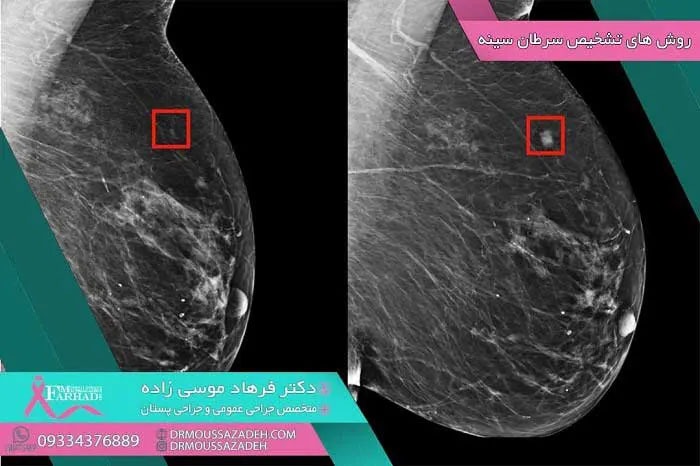

Some types of breast cancer may cause a lump in the breast. You can better check your situation regarding this disease by studying the signs and symptoms of cancer. Most breast cancers are detected early in screening mammograms before they are felt and before symptoms appear.

There are different types of breast cancer, among which, non -invasive ductal carcinoma (DCIS) and invasive carcinoma are more common, and others such as phyllodes tumors and angiosarcoma are less common in patients. After sampling, breast cancer cells are tested for proteins called estrogen receptors, progesterone receptors, and HER2. Tumor cells are also examined in the laboratory to determine the stage of cancer. Specific proteins present and determination of tumor grade help in deciding treatment options.

Knowing what the breasts should look like is an important part of breast health. Although it is important to have regular screening tests to detect this cancer, mammograms do not find every type of breast cancer. Therefore, it is very important to be aware of your breast changes and know the signs and symptoms of breast cancer .

The most common symptom of breast cancer is the presence of a new lump . A painless hard lump with irregular edges is more likely to be cancerous, but breast cancer lumps can also be soft or round. They can even be painful. It is very important to have any type of lump or changes in the breast checked by a specialist.